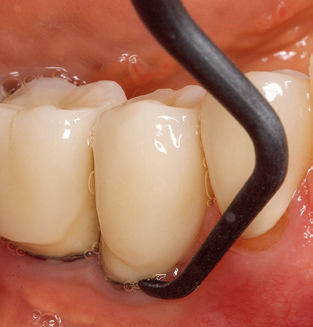

L'attuale piano di lavoro per SPT

L'aggiornamento della storia medica del paziente è un aspetto importante di SPT e dovrebbe avvenire almeno una volta all'anno. Aiuta il team dentale a identificare e documentare eventuali nuovi fattori di rischio. Soprattutto quando un paziente viene curato per molti anni, è importante stabilire se i fattori di rischio per la salute specifici del paziente e generali sono cambiati. Ciò riguarda principalmente un aumento del rischio a causa del diabete, ma altre condizioni generali (malattie cardiovascolari e neoplasia) possono anche produrre un profilo di rischio modificato a seguito del trattamento eseguito e della somministrazione dei farmaci. Di conseguenza, l'aggiornamento della storia medica come parte di SPT è molto importante, poiché un profilo di rischio modificato può innescare la necessità di adattare l'intervallo di trattamento. Nel passaggio successivo, è importante prestare la dovuta attenzione alla diagnostica. Mentre gli strumenti sono un aspetto centrale di SPT, i risultati e la loro documentazione non devono mai essere trascurati. I risultati parodontologici sono essenziali per una buona diagnosi; aumenti della profondità della tasca e l'indice BOP sono chiari indicatori dell'avanzamento della malattia parodontale e perimplantare. Pertanto, il team non dovrebbe evitare di sondare anche gli impianti, con l'obiettivo di raccogliere i dati richiesti. Allo stesso tempo, è importante utilizzare sonde parodontali con segni millimetrici. Le sonde metalliche sono già state utilizzate per determinare la profondità della tasca attorno ai denti naturali per decenni. Nel caso degli impianti, la sfida di registrare profondità delle tasche corrette e riproducibili è ancora maggiore. Poiché la discrepanza tra il diametro dell'impianto e il contorno della sovrastruttura si traduce regolarmente in un over-contouring della sovrastruttura, le sonde flessibili che presentano ancora marcature millimetriche sono una soluzione sensata per misurare la profondità della tasca attorno agli impianti (ad es. Colorvue Kit PCV11KIT6, HuFriedy; Fig. 4 ).

Nei pazienti senza particolari fattori di rischio, lo stato PERIO completo deve essere documentato almeno una volta all'anno. In casi con più fattori di rischio (diabete, fumo, ecc.), un monitoraggio più regolare (ogni sei mesi) può rivelarsi prudente.